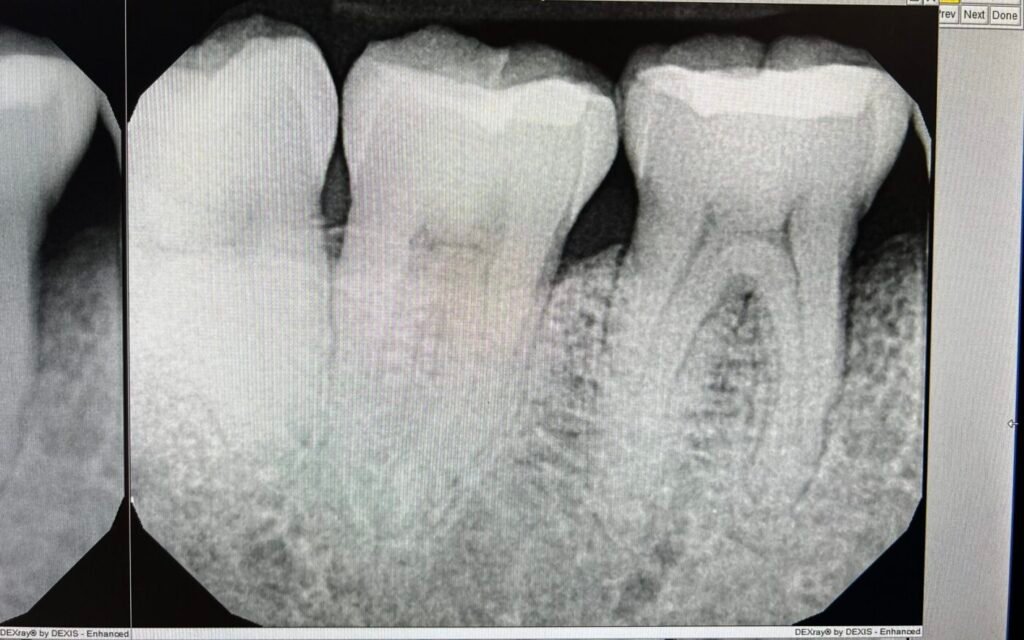

We perform a detailed exam, measuring gum pockets and using digital X-rays to assess bone density and the extent of the infection.